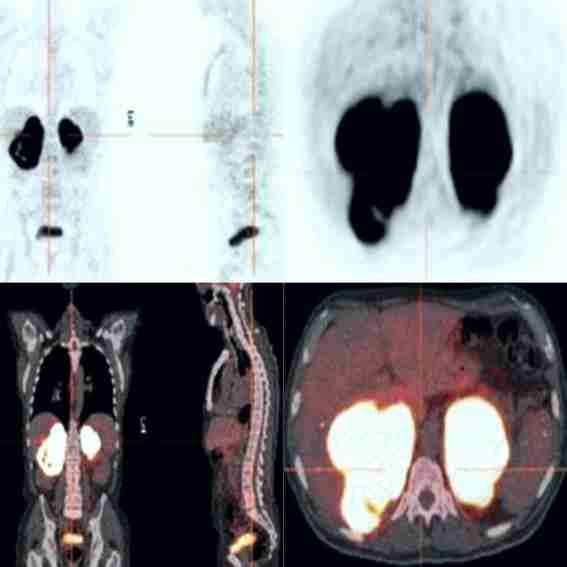

La ecografía abdominal demostró tumores en ambas glándulas suprarrenales. Este hallazgo fue confirmado por imágenes de la tomografía computada que identificaron tumoraciones grandes, heterogéneas y necróticas en ambas glándulas suprarrenales con contornos lobulados (11 x 8 x 7 centímetros de diámetro para la glándula suprarrenal derecha y 9 x 6 x 5 centímetros de diámetro para la glándula suprarrenal izquierda), sin evidencia de linfadenopatías retroperitoneales o afección visceral (figura 1). Las imágenes de tomografía computarizada del resto del cuerpo fueron negativas para cualquier linfadenopatías o compromiso de otros órganos. La tomografía por emisión de positrones mostró captación intensa de fluorodesoxiglucosa en ambas glándulas suprarrenales sin captación por los ganglios linfáticos paraaórticos retroperitoneales (figura 2). La radiografía de tórax, la endoscopia superior y la colonoscopia no mostraron hallazgos anormales.